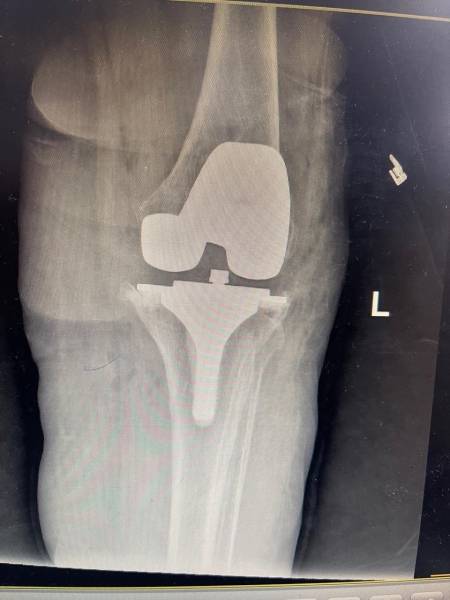

- إجراء عمليات جراحية معقدة و دقيقة في مجال العظام و المفاصل و الكسور و الإصابات ، رغم الضغط الكبير على المستشفى و أعداد المراجعين الكبيرة.

- تطبيق تقنيات جراحية حديثة و متقدمة، و ذلك في ظل التحديات التي يواجهها الفريق بسبب أعداد المرضى و المراجعين الكبيرة.

- تقديم خدمات جراحية عالية الجودة و آمنة للمرضى، رغم الضغط الهائل على المستشفى في العيادة و القسم و الطوارئ .